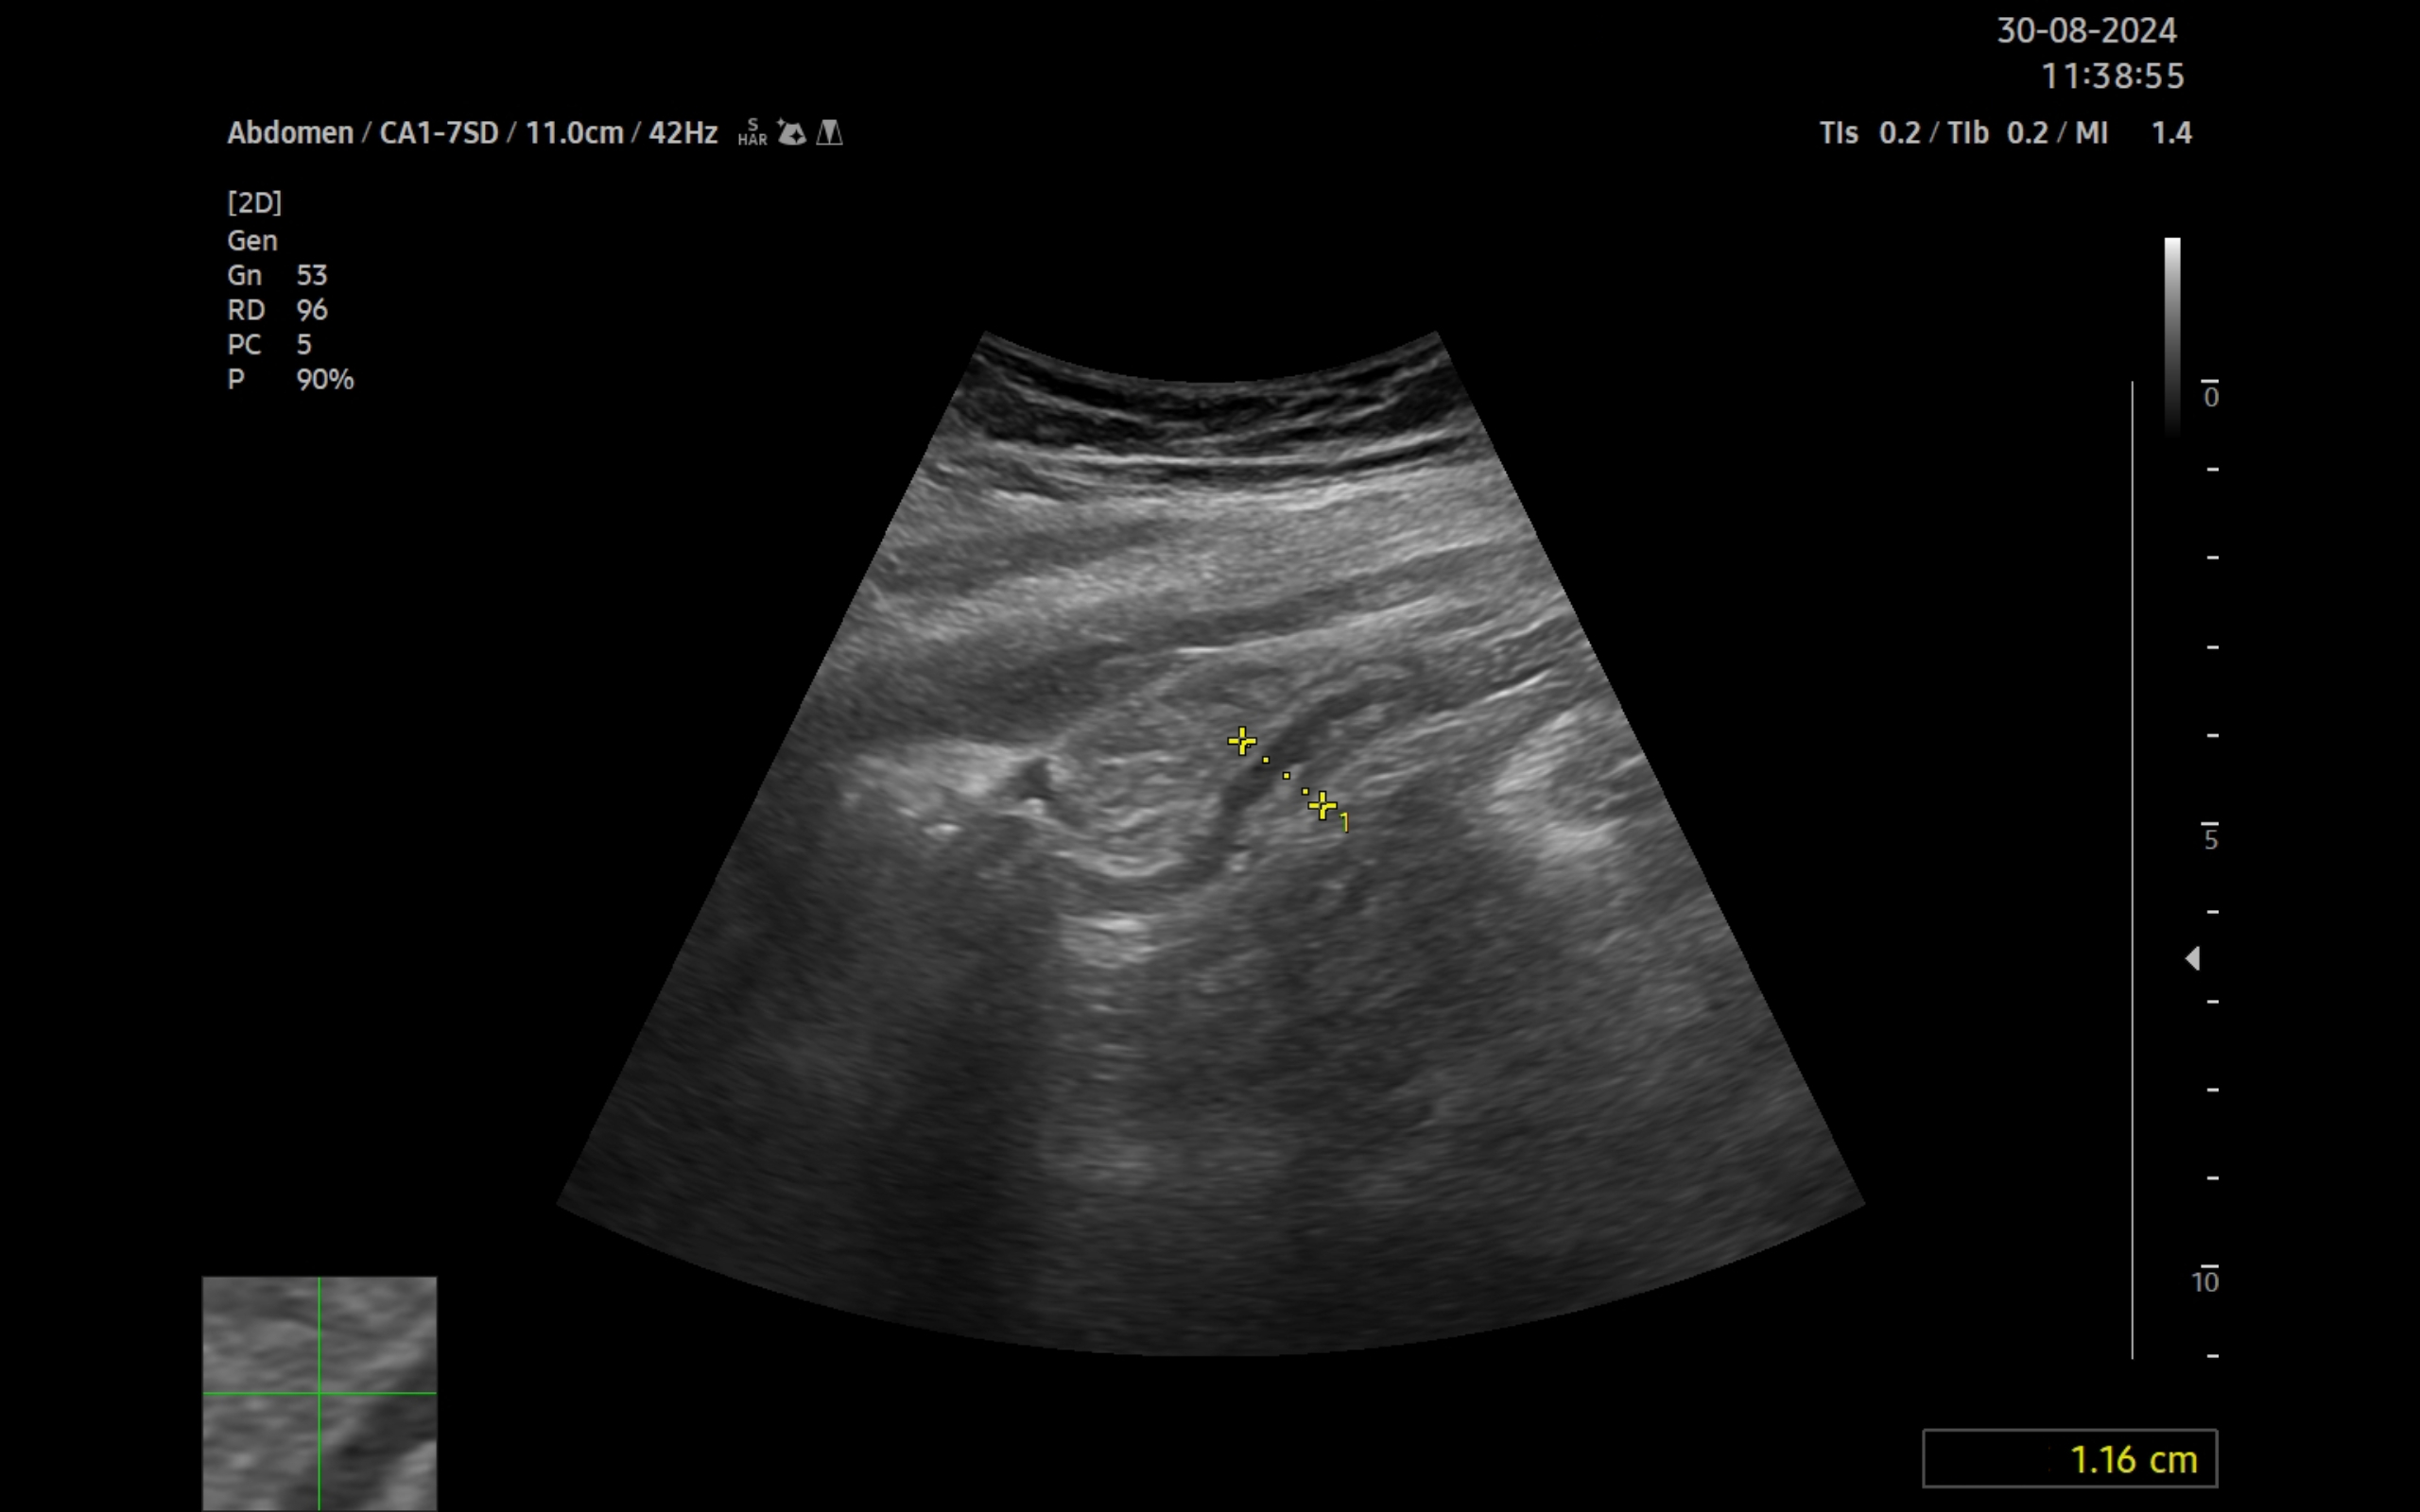

Ecografía clínica:

Imagen hiperecogénica con sombra en interior de vesícula biliar, hígado, páncreas, bazo y riñones sin alteraciones, vejiga orina poco replecionada. Llama la atención mínima imagen anecogénica en fondo de saco de Douglas. Apéndice visible en fid con diámetro 1,07 cm con captación aumentada con apendicolito con fenómeno centelleo.